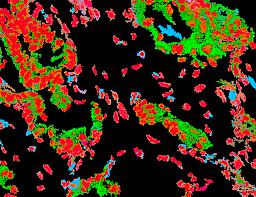

Pancreatic ductal adenocarcinoma is a lethal disease with limited treatment options and poor survival. We studied 83 spatial samples from 31 patients (11 treatment-naïve and 20 treated) using single-cell/nucleus RNA sequencing, bulk-proteogenomics, spatial transcriptomics and cellular imaging. Subpopulations of tumor cells exhibited signatures of proliferation, KRAS signaling, cell stress and epithelial-to-mesenchymal transition. Mapping mutations and copy number events distinguished tumor populations from normal and transitional cells, including acinar-to-ductal metaplasia and pancreatic intraepithelial neoplasia. Pathology-assisted deconvolution of spatial transcriptomic data identified tumor and transitional subpopulations with distinct histological features. We showed coordinated expression of TIGIT in exhausted and regulatory T cells and Nectin in tumor cells. Chemo-resistant samples contain a threefold enrichment of inflammatory cancer-associated fibroblasts that upregulate metallothioneins. Our study reveals a deeper understanding of the intricate substructure of pancreatic ductal adenocarcinoma tumors that could help improve therapy for patients with this disease.